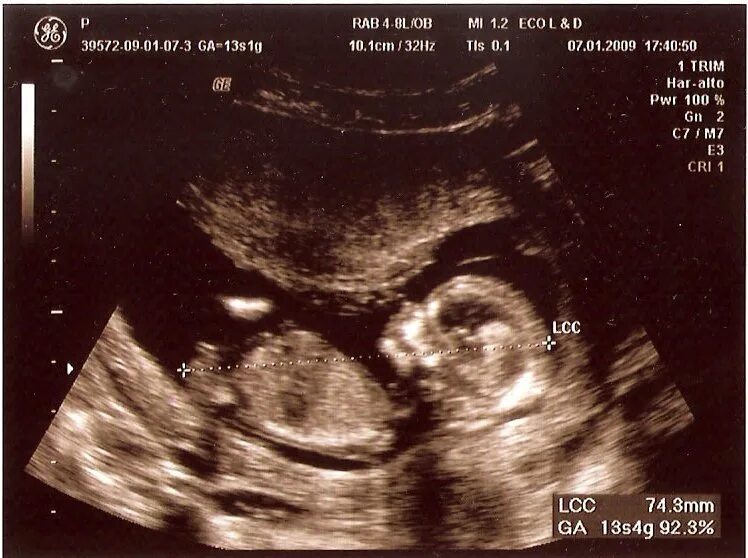

Ребенок в 13 недель